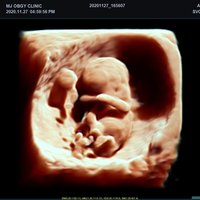

Mit dem X-CUBE 90 beginnt ALPINION eine neue Generation an Farbdopplersystemen, die X- CUBE Serie. Mit Bildverarbeitungstechnologien eines Premiumsystems und neuen Breitband- Schallköpfen mit X + Crystal Signature™ Technologie wartet das neue X-CUBE 90 auf.

Neben der hohen Bildqualität liegt ein weiterer Fokus auf der Vereinfachung und der Anpassung der Bedienung des Ultraschallgeräts. Individuell programmierbare Workflows und ein erweitertes Spektrum an automatisierten Messungen ermöglichen ein schnelleres und genaueres Arbeiten in jeder Situation.

X + Architecture

Die X + Architecture ist eine erstklassige Imaging-Plattform, die durch die Kombination von X + Crystal Signature™, der Schallkopftechnologie mit hoher Sensitivität und Breitbandigkeit, und X + FIT, ALPINIONs modernste Beamforming- und Datenverarbeitungstechnologiengeschaffen wurde. X + FIT ist eine neue Technologie, die den Schallstrahl scharf fokussiert sendet, ein großes Datenvolumen empfängt und mit hoher Geschwindigkeit verarbeitet. Darüber hinaus nutzt X + Crystal Signature™ Einkristalle und unser eigenes entwickeltes Schallkopfmaterial, um eine hervorragende Brillanz zu erzielen und die Diagnosemöglichkeiten zu erweitern.

• SVC1-8H (1-8 MHz) für Ultraschalluntersuchungen in Bereichen Abdomen, Geburtshilfe, Gynäkologie, Urologie, Pädiatrie, EM